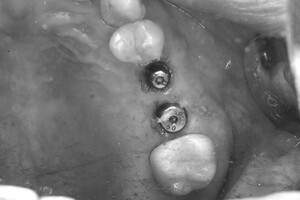

症例写真-2

- Befor

- 途中経過

- After

| 治療方針 | 右下の当該歯は歯根破折により保存不可能と診断しました。歯周疾患も伴っていたため抜歯後に骨吸収※1が大きく起こることが予測できました。チタンメッシュ併用骨再生誘導法(GBR※2)を選択しインプラント埋入と同時に行い自然な歯槽骨のラインを再現しました。またGBRを行う際にインプラント辺縁の付着歯肉の減少が起こる為、遊離歯肉移植術(FGG※3)を行い清掃性を考慮した形態に仕上げました。 ■治療方針の解説 治療した右下の歯をレントゲンで撮影したところ根本の部分に黒く写る箇所があり「根尖性慢性周囲炎※1」と診断。また歯周病も進行していました。 ※1 骨吸収・・・歯槽骨という歯を支える骨がなくなっていくこと |

| 担当者所見 | 主訴の右下だけでなく歯茎の腫れ、発赤があり不良補綴や不良充填など他にも治療箇所が多数ありました。プラークコントロールが不良であった為まずはブラッシング指導を行いセルフケアの重要性を理解していただくところからスタートしました。 右下6番の歯はインプラント治療を行なった結果審美的にも機能的にも患者様の満足を得ることができました。骨造成と歯肉移植も行なった為インプラントを支える十分な歯周組織の獲得ができたと思っております。 |